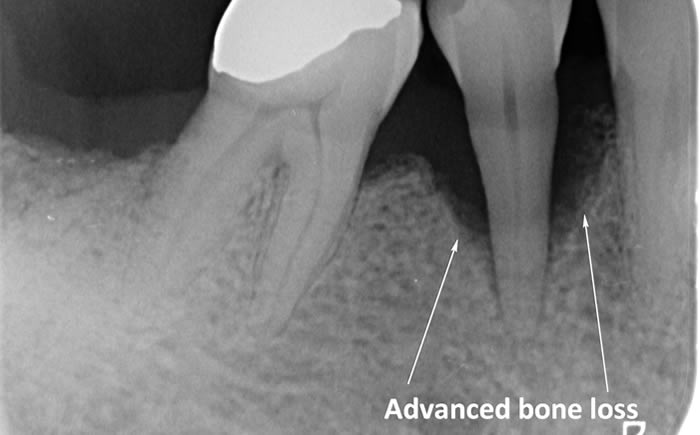

The diagrams below show the different stages of gum disease

Periodontitis is a more advanced stage of gum disease where there has been damage to the bone which supports the teeth. If left untreated periodontitis leads to more and more bone loss until the teeth start to become loose and eventually fall out by themselves or need to be extracted by a Dentist.

The main cause of gum disease is plaque. Plaque consists of millions of bacteria which live on and around the teeth and gums. These bacteria produce toxins which damage the gums. To begin with the gums start to peel away from the teeth and “pockets” form. As the bacteria penetrate deeper into these “pockets” they then start to cause damage to the bone which holds the teeth in. As more bone loss occurs the teeth start to become increasingly looser until they eventually start to fall out one by one.

In cases of advanced gum disease our Hygienist’s will also carry out deep scaling which cleans the root surfaces beneath the gum level. When pockets develop in the gums around the teeth plaque bacteria and calculus form on the root surfaces of the teeth and are protected from toothbrushing by the overlying gum. However, our Hygienist’s have special thin scaling instruments which can go down inside the pockets to clean the root surfaces. This treatment is carried out in small sections under local anaesthetic to ensure that you are comfortable throughout the treatment.